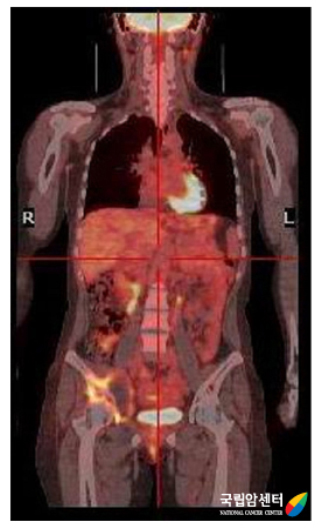

최근에 연부 종양의 진단에 적용하려는 연구들이 많이 보고 되고 있습니다. 양전자방출단층촬영(PET)은 기존의 검사법에 비하여 원격 전이의 진단에 정확성이 높은 검사이며, 연부조직 육종의 전이 및 재발여부를 판단하는데 좋은 검사입니다.

[ 양전자방출단층촬영 ]